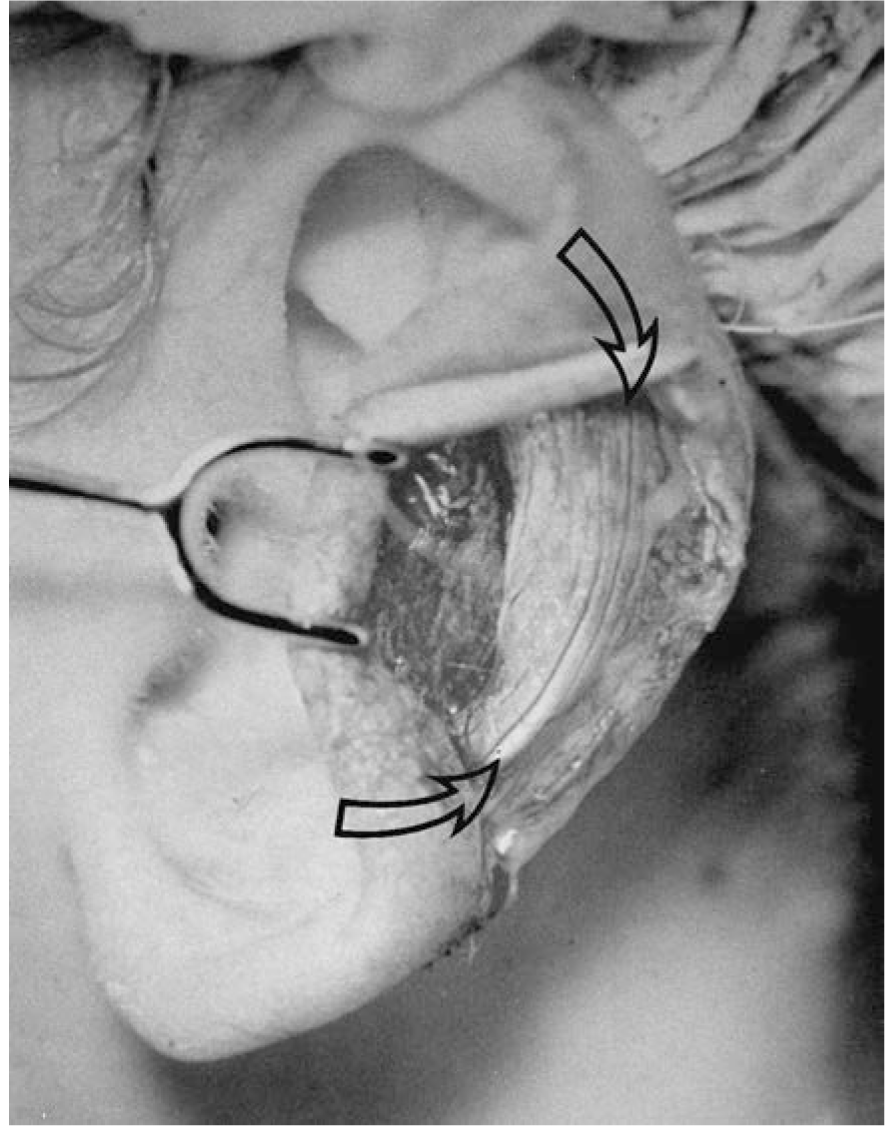

Stahl Ear. Various techniques have been described to excise the extra crus. This author prefers the technique described by Kaplan and Hudson.9 An incision is made inside the helical rim, the lateral skin is carefully dissected off the cartilage, the extra crus is excised, and the cartilage defect is closed primarily. The excised cartilage can be used as an onlay graft to reconstruct the superior crus of the triangular fossa (Figure 49.9).

FIGURE 49.9. Technique for repair of Stahl’s ear. (With permission from Thorne CH, Wilkes G. Otoplasty, ear deformities and ear reconstruction. Plast Reconstr Surg. 2012;129(4):701e, Figure 3.)